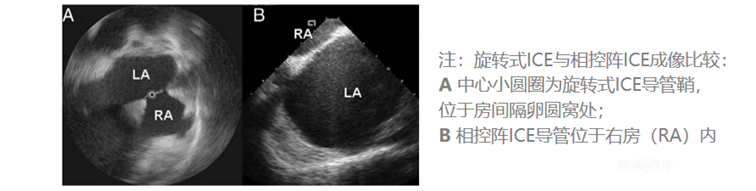

ICE使用5~12MHz的超声频率,理论最高分辨率可以达到0.1mm、且同时具有最高16cm的心内穿透成像深度。常见的2D ICE导管分为单阵元旋转超声导管、电子相控阵列超声导管两类,目前后者在临床上更为常用。目前ICE导管直径为8~10Fr。

就2D ICE来说,相控阵ICE相比单阵元旋转ICE具有以下优势:更深成像深度、获取多普勒血流彩超的能力。相控阵ICE因而在2D ICE当中更受青睐。